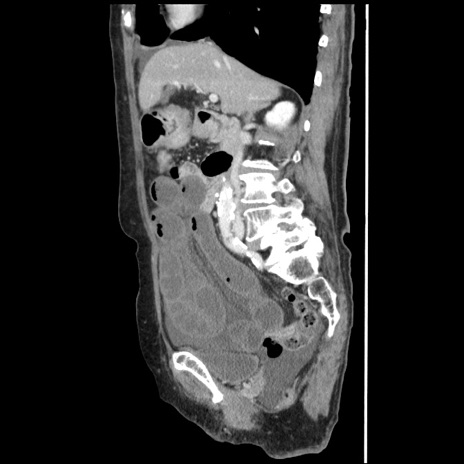

横断像

冠状断像